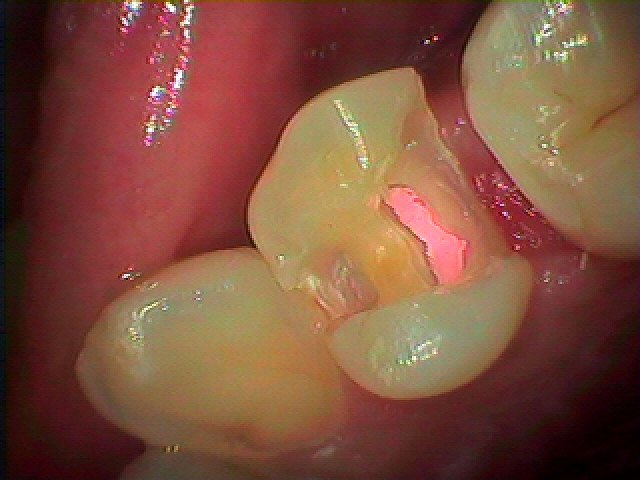

4番の遠心部に虫歯が存在しています

このように大きく中は空洞化していました

神経に虫歯が達しており、根の治療となりました